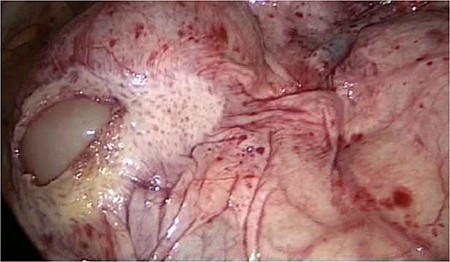

The laparoscopic anterior resection was performed in February 2019. The patient was positioned in a modified lithotomy position. The pneumoperitoneum was established by a Veress needle. The trocars were placed umbilical, two on the left and one on the right abdominal wall. The descending colon and the endoscopic ink-marked region were visualized perfectly. While getting an overview of the abdominal cavity, we noticed an abnormality in the ileum region. It seemed that the peritoneum was covering the entire ileum. The situs is depicted in Figs 1–4.

The entire small bowel was found retroperitoneal covered by a slim peritoneal layer (Fig. 1). The dorsal peritoneum covering the ileum was opened (Fig. 2).

Even the terminal ileum seemed to be retroperitoneal. The slim preperitoneal appendix and the terminal retroperitoneal ileum are demonstrated in Fig. 4. The entire ileum was covered by the peritoneum.